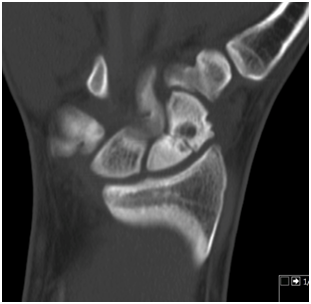

The arthroscopic procedure started with the realization of standard radio-carpic initial portals; medium-carpal portals helped with the identification of the pseudarthrosis focus (Figure 4). The pseudarthrosis focus was blown out (Figures 5 & 6). The spongious graft of the contralateral iliac crest was harvested. Placement of the graft through the midcarpal portal of visualization by adapting the arthroscopy trocar (Figures 7-9). The traction was withdrawn. The graft was fixated with a percutaneous anterior approach and arthroscopic support and placement of the double compression screw with radiographic support (Figure 10).

Figure 5 Arthroscopic debridement.

Figure 6 Arthroscopic view after debridement.